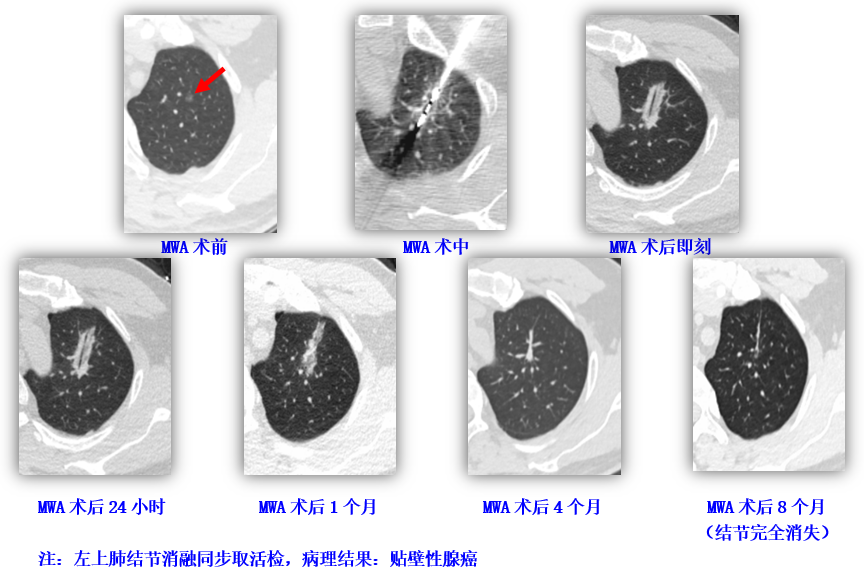

▲左上肺结节右肺术后1月行微波消融(MWA)治疗

MWA治疗过程及效果:

治疗效果理想:

注:血清学肿瘤标示物CEA在右下肺结节手术切除后依然持续升高,在左上肺结节消融治疗后恢复正常。

注:右下肺结节在传统胸腔镜手术切除后,患者肺功能遭到显著破坏。左上肺结节行消融治疗前后,肺功能无明显改变,消融治疗肺结节对患者肺功能具有显著的保护作用。